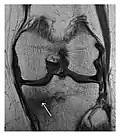

Figure 8: Proximal diaphyseal fatigue fracture of the tibia in a 20-year-old man with a history of regular jogging. (a) Lateral radiograph shows no obvious fracture lines but a subtle localized medial tibial cortex periosteal reaction (arrows). (b) Sagittal reformatted CT image acquired 1-month after the radiograph shows a linear hypoattenuation in the tibial cortex (arrowhead), as well as obvious periosteal thickening (arrows). (c) Sagittal T2-weighted fat-saturated image acquired the same day shows an area of hyperintensity spreading over the proximal tibia (arrows), which is consistent with the presence of proximal tibial fracture.[1]

Figure 9: Proximal metaphyseal fatigue fracture of the tibia in a 27-year-old recent male military recruit. (a) Anteroposterior radiograph is within normal limits. (b) Coronal T1-weighted MR image shows a marked linear hypoattenuation along the medial tibial metaphysis (arrow) surrounded by diffuse hypointensity in keeping with posttraumatic edema.[1]